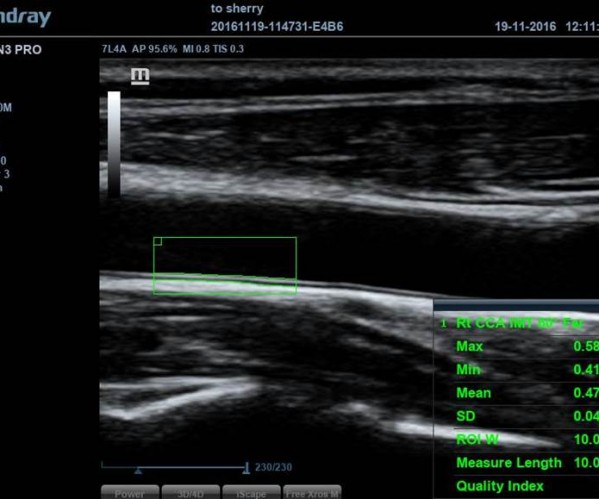

![]() Auto IMT

경동맥 내중막 두께 자동으로 측정하는 기능